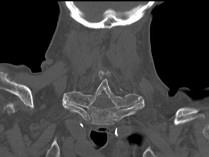

问题 男,92岁,下腰不适伴晨僵半年余,请结合影像学检查,选出最可能的诊断 ( )

选项 A、阻滞椎 B、类风湿关节炎 C、强直性脊柱炎 D、化脓性脊柱炎 E、脊椎退行性变

答案 C